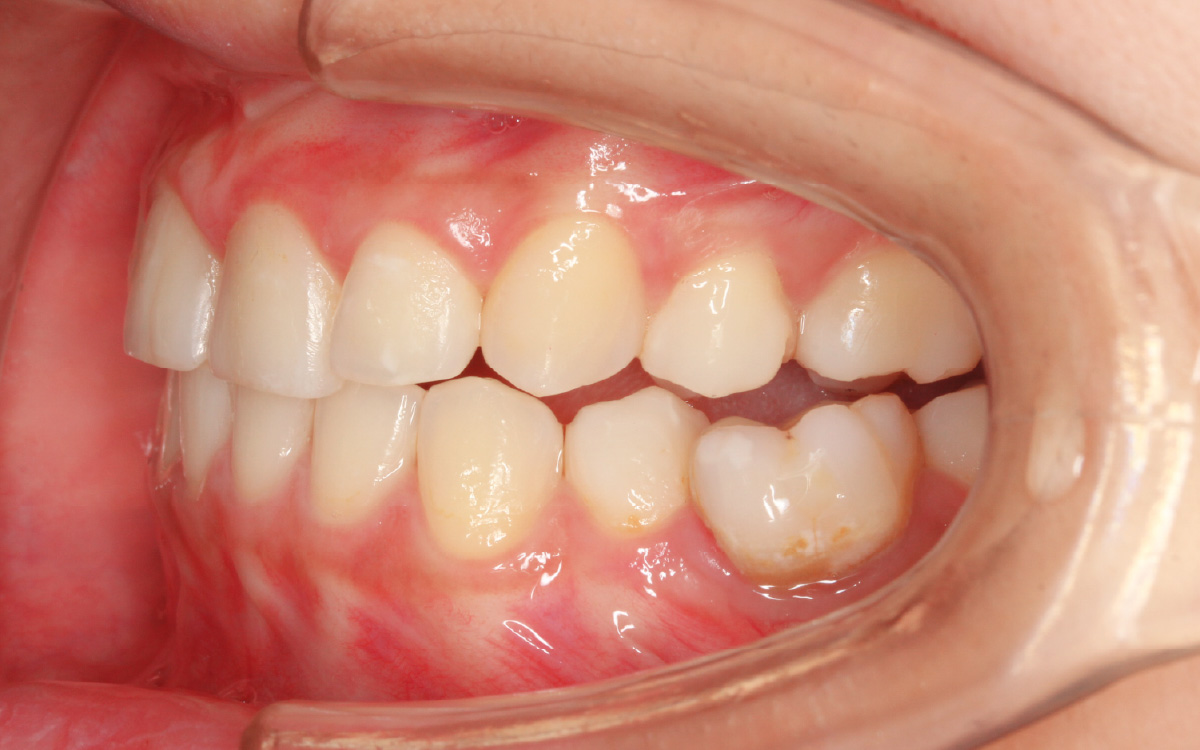

スプリント後口腔内写真

治療前

口腔内写真

口腔内の咬み合せも変化しており、顎関節の状態と口腔内の咬み合せが密接に関係していることがよくわかります。

ここまで進行した円板転位が常に改善するわけではありませんが、患者さんがスプリントを24時間使用してくれたおかげでこの様な変化が起きました。